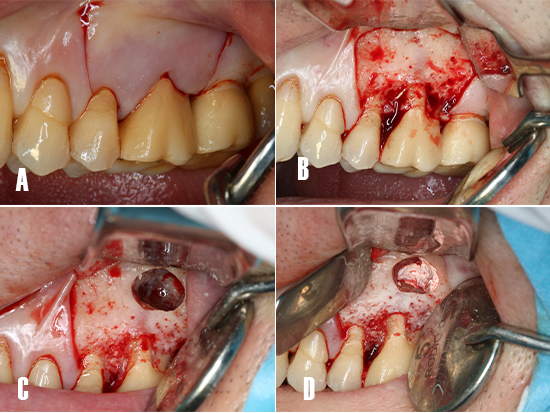

La cirugía se realizó bajo anestesia local infiltrativa con articaína al 4% (1:100,000) (Inibsa; Lliça de Vall, Barcelona, Spain). Se realizó una incisión a espesor completo con una hoja bisturí 15c, para elevar un colgajo mucoperióstico de Newmann trapezoidal. Tras la elevación del colgajo se realizó una osteotomía con una fresa redonda de carburo tungsteno 0.27mm de diámetro (Jota AG, Rüthi SG, Switzerland) empleando una pieza de mano recta 1:1 (Synea Vision, W&H Dentalwerk, Bürmoos, Austria). Tras acceder a la cripta ósea, se realizó la resección de la porción apical de las raíces, se instrumentó una cavidad retrógrada de 3 mm de profundidad con puntas ultrasónicas (Piezomed, W&H Dentalwerk, Bürmoos, Austria). La hemostasia se realizó empleando gasas estériles impregnadas con epinefrina (B. Braun, 1 mg/ml; Rubí, Barcelona, Spain) y con tiras de politetrafluoretileno (PTFE) previamente esterilizadas en autoclave, y que se compactaron dentro de la cripta ósea (Fig. 4).

Figura 4. Técnica quirúrgica. A) Incisión a espesor total para elevar un colgajo de Newmann trapezoidal. B) Despegamiento del colgajo. Se observa la cortical vestibular intacta. C) Ostectomía de acceso a la cripta ósea, nótese el tamaño de la lesión. D) Hemostasia: esta se obtiene aplicando gasas impregnadas con epinefrina y tiras de PTFE compactadas hacia las paredes de la cripta ósea, y surte un efecto de barrera mecánica.

La cavidad retrógrada se secó con puntas de papel estériles y luego se obturó con mineral trióxido agregado (MTA, Dentsply Tulsa Dental, Tulsa, OK, USA). Se colocaron membranas de A-PRF+ para rellenar la cripta ósea y para cubrir la ostetomía de acceso. El colgajo se suturó con puntos interrumpidos empleando seda no reabsorbible (Fig. 5).

Figura 5. Obturación retrógrada. A) Cavidades apicales son obturadas con MTA. B) La cripta ósea se rellena con membranas de A-PRF+. C) La osteoctomía es cubierta con una membrana de fibrina rica en plaquetas. D) Sutura del colgajo con puntos interrumpidos.